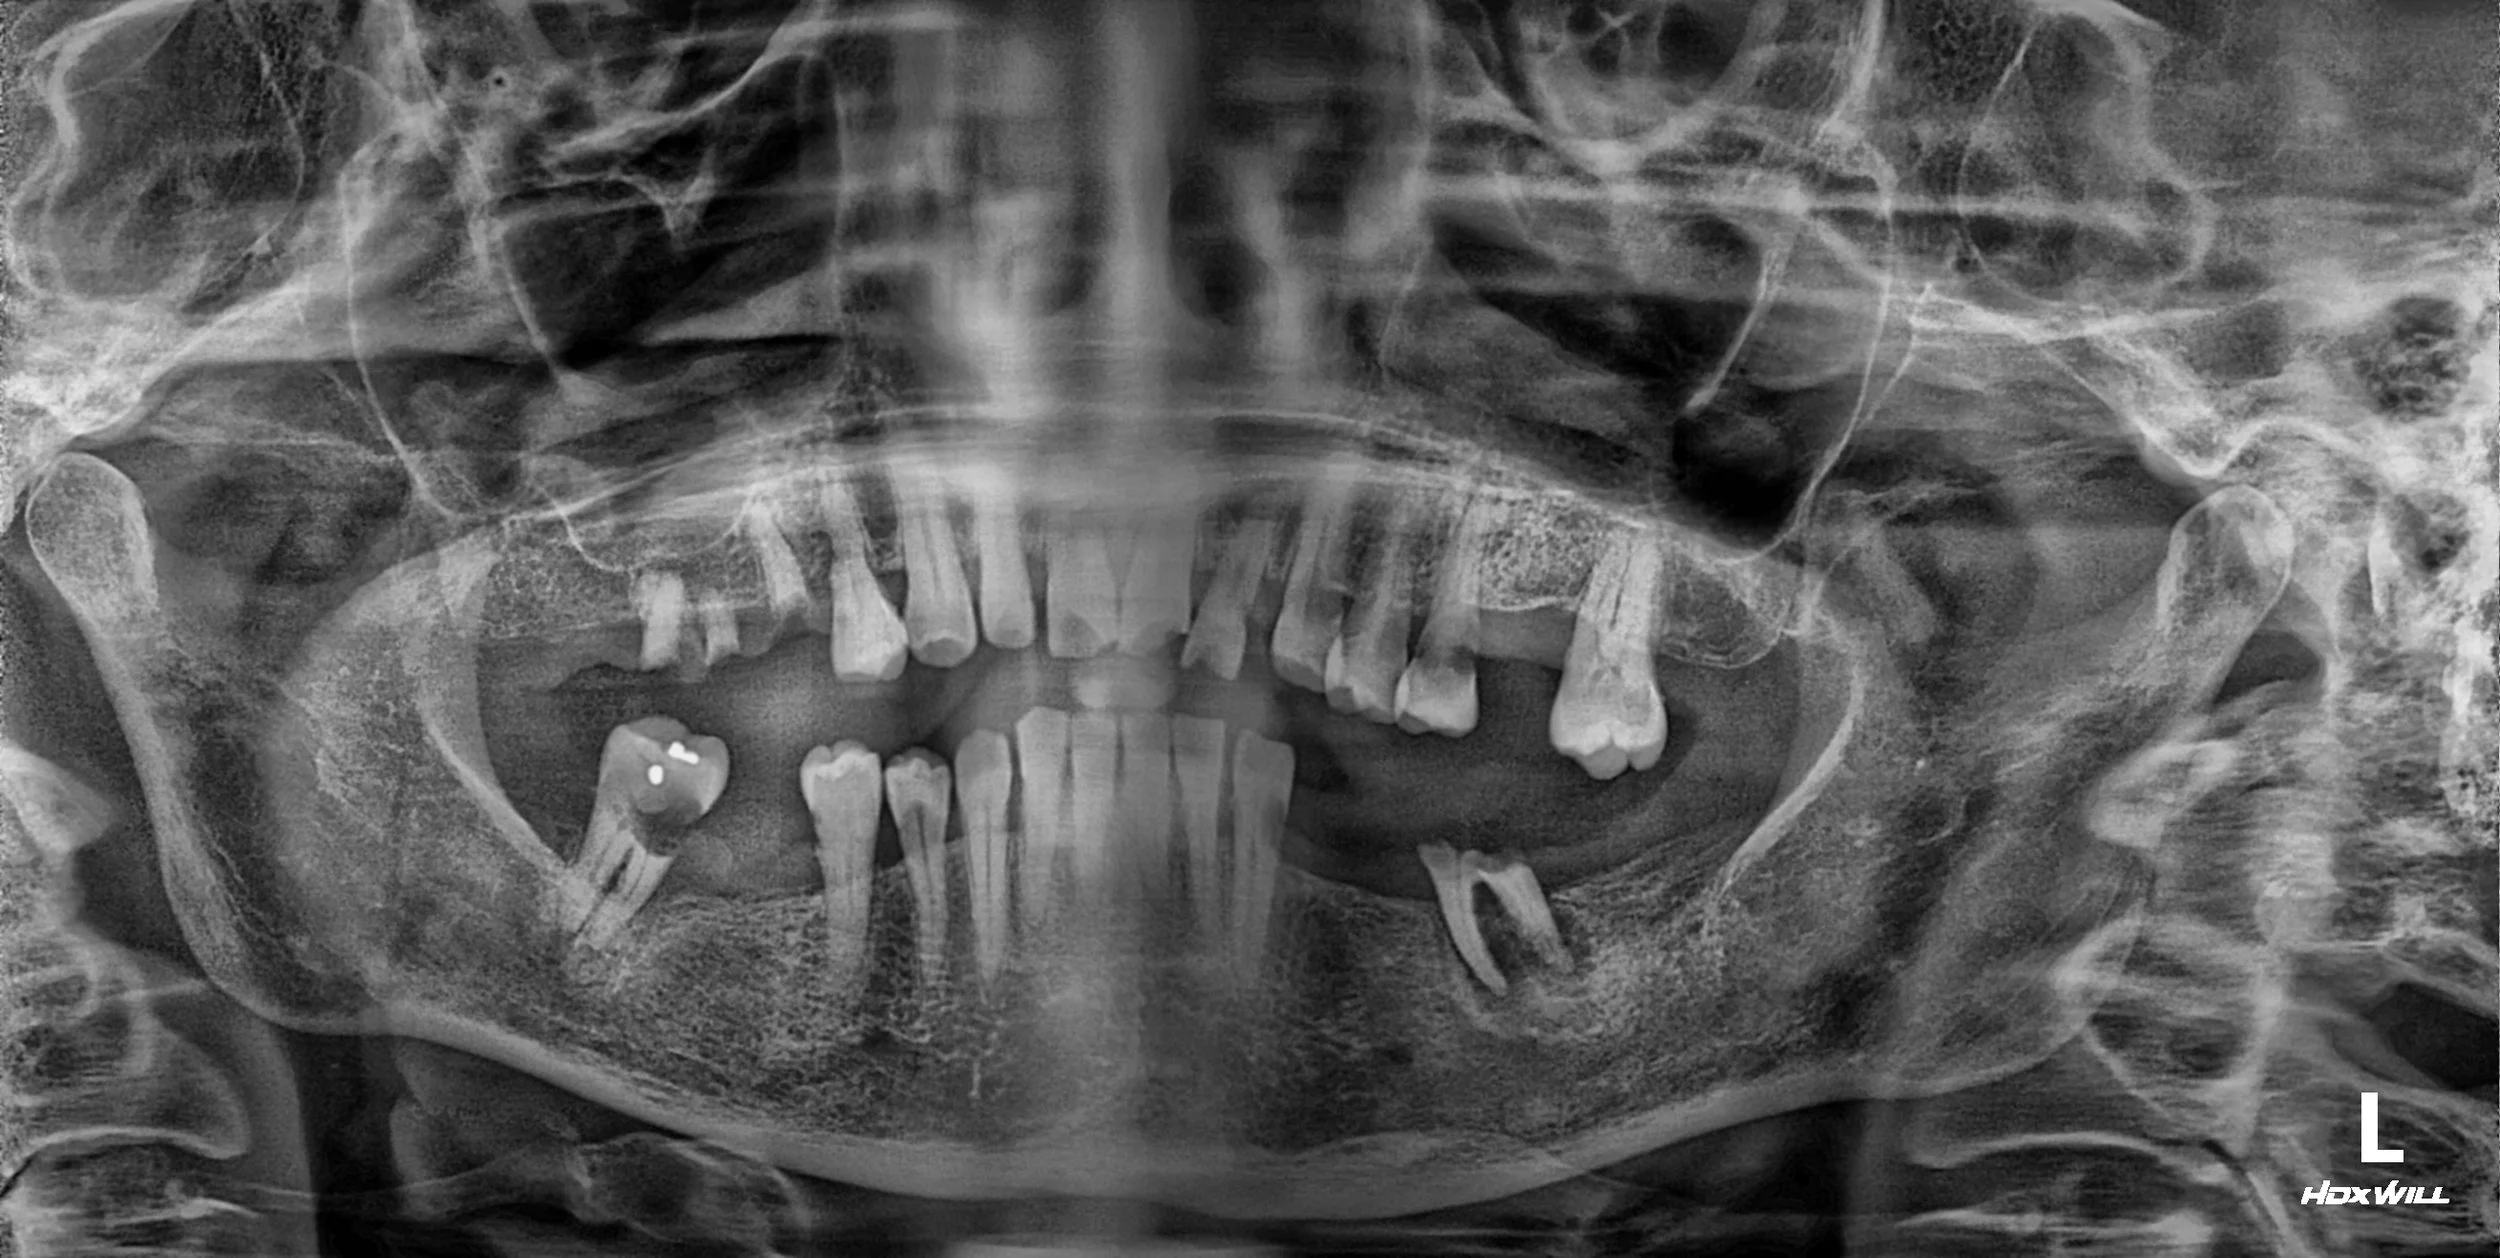

OPG - BEFORE

• Posterior Reconstruction (GBR & Implants): To rebuild the alveolar foundation in the molar regions via Guided Bone Regeneration (GBR) and strategic implant placement.

1. Initial Phase: Comprehensive periodontal therapy was conducted to create a healthy environment. Hopeless units were removed, and remaining natural teeth were stabilized.

2. Surgical Phase: Extensive bone grafting (GBR) was performed in the posterior segments to compensate for severe atrophy. Following integration, dental implants were placed to serve as the primary occlusal anchors.